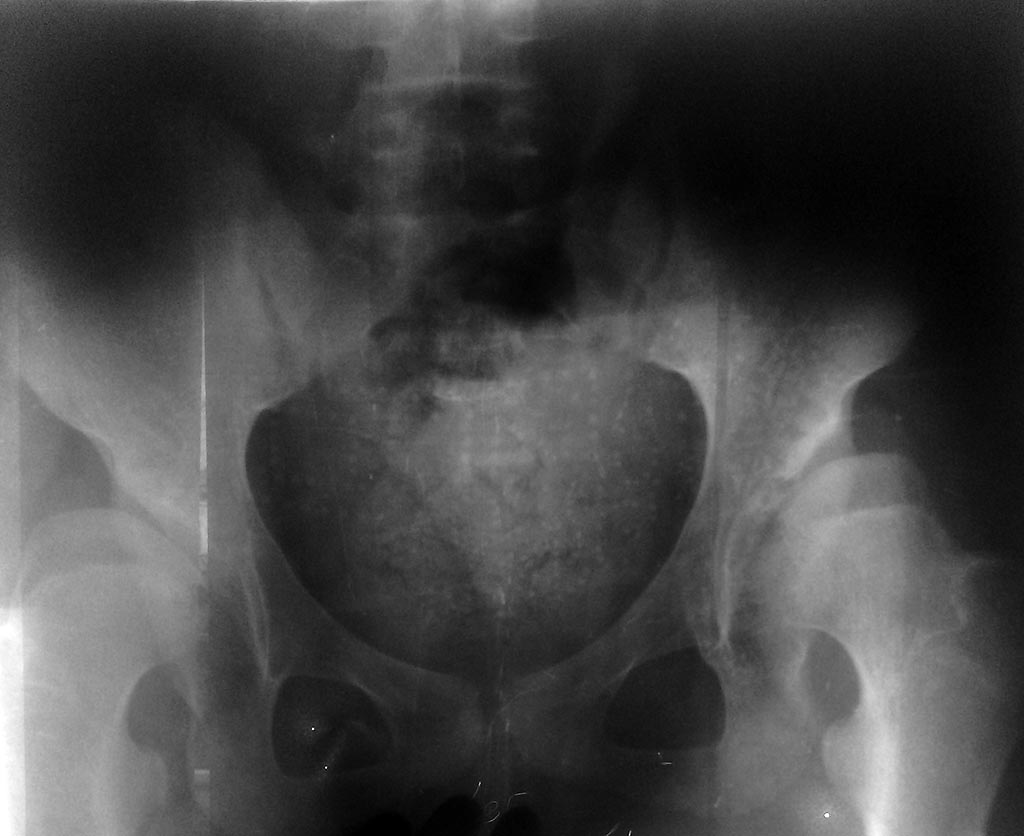

Здравствуйте,многоуважаемые коллеги, у нас такой случай: Больная М. 13 лет.

Лечилась консервативно с диагнозом "Врожденный двухсторонный вывих бедра" На данный момент отмечается( смотрите на рентгенограмму) латеропозиция (половина головки бедра находится вне вертлужной впадини) недоразвитие вертлужных впадин, клинически - контрактура небольшом обёме, редкие боли.Что вы посоветуете.